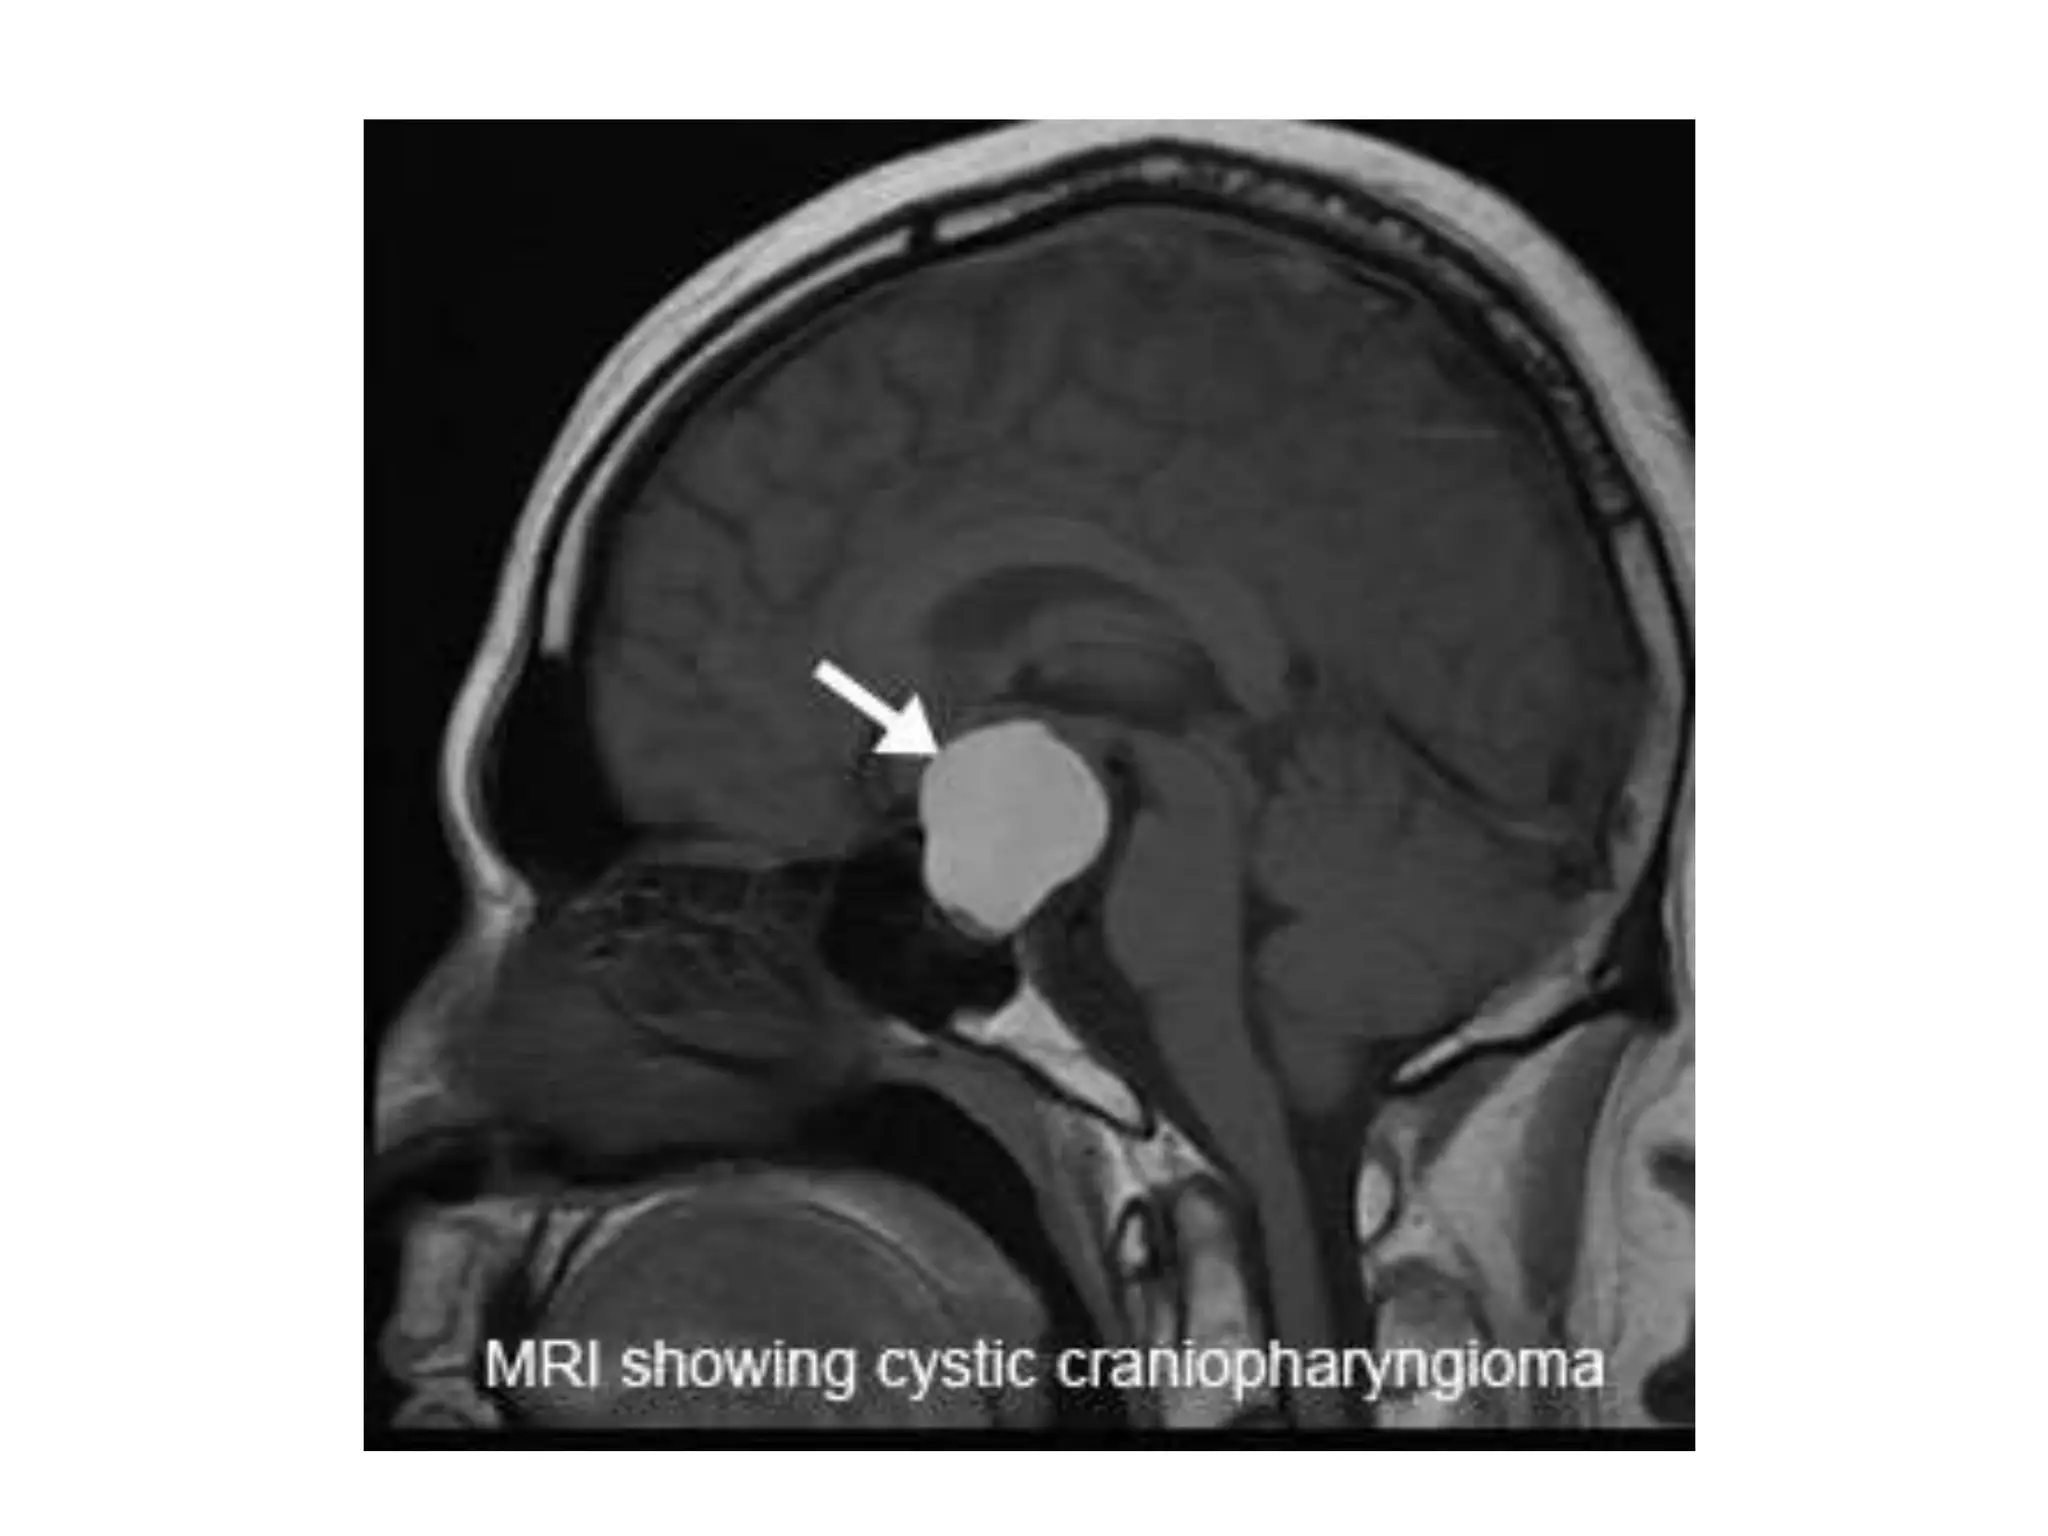

5) Congenital tumor of the gland

(Craniopharyngioma)

Development:

A tumor arises from a remnant of Rathke's

pouch. *

Effect:

• Increasing the intracranial pressure;

hydrocephalus

• Disrupting the function of the pituitary gland

• Damaging the optic nerve

5) Congenital tumorof the gland (Craniopharyngioma) Development: A tumor arises from a remnant of Rathke's pouch. *

Effect: • Increasing theintracranial pressure; hydrocephalus • Disrupting the function of the pituitary gland • Damaging the optic nerve